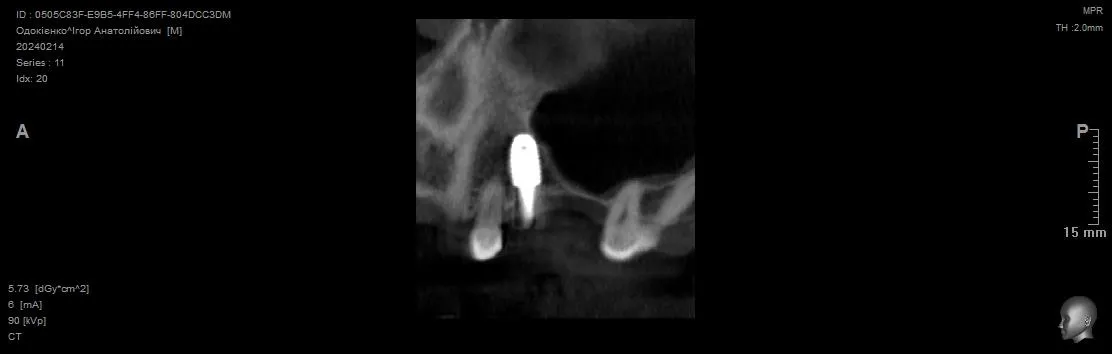

Видалення зуба 3.4 + Імплантація 3.4 3.5 3.7. Формувачі ясен. Система Neobiotech